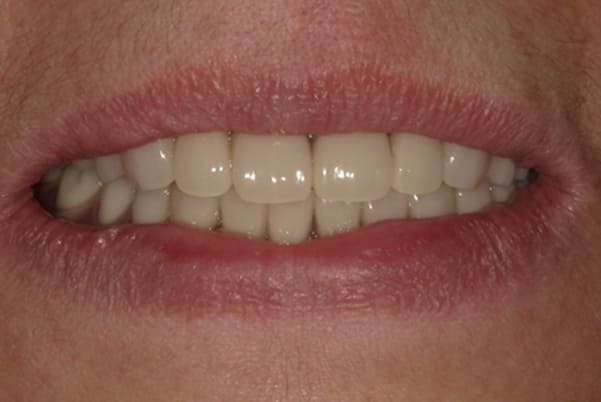

治療前後の口元の比較

こちらは、口を少し開いた時の治療前と治療後の

口元です。

正面から見た時にクラスプが目立たないように、

歯ぐきになじむ素材にて入れ歯を製作し、痛くなく自然に馴染み快適に生活を送れるようになりました。